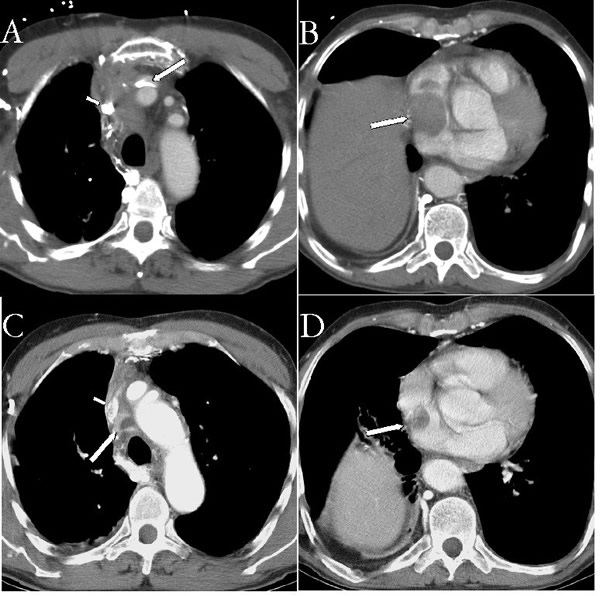

| Figure 1A Pre chemotherapy CT showing tumor at the confluence of the innominate veins (see arrows). | Figure 1B Pre chemotherapy CT showing tumor extending down into the right atrium (arrow). |

His physical examination was significant for head and upper extremity swelling, jugular venous distention without A or V waves, and superficial varices over the thorax. A computerized tomography (CT) scan (Figures 1A and 1B) demonstrated a mass in the mediastinum involving the superior vena cava (SVC) and extending into the right atrium. Echocardiography confirmed the intracardiac component. The patient was started on neoadjuvant therapy consisting of cisplatin, cyclophosphamide, and doxorubicin with plans for postoperative radiation therapy. A post chemotherapy CT scan demonstrated shrinkage of the mass (Figures 1C and 1D). A preoperative venogram confirmed the occluded SVC and well formed collaterals (Figure 2).